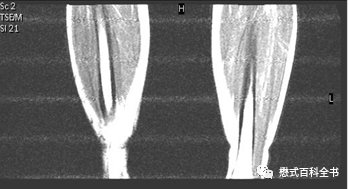

图16~18:线圈及单元故障导致的伪影

对于多通道线圈,如果某些单元或者通道产生故障,则对应的位置图像信号有异常。一般通过更换线圈、排查能够识别。

解决这种伪影当然从源头入手,更好线圈或者维修线圈。